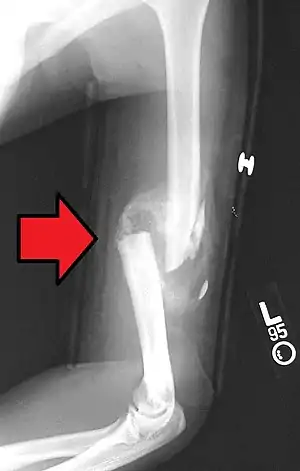

A transverse fracture of the humerus shaft

A spiral fracture of the distal one-third of the humerus shaft